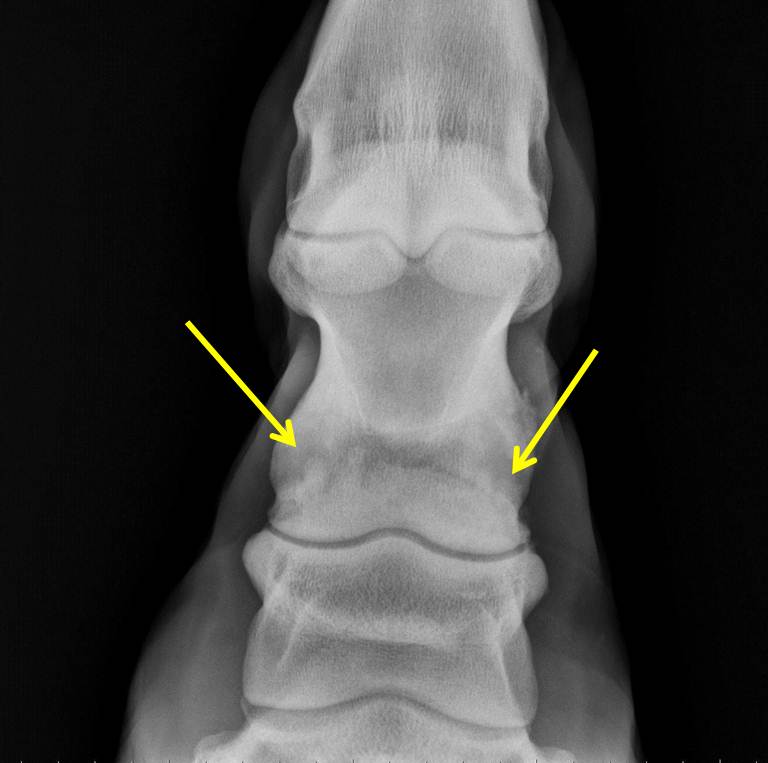

Osteoarthritis is a chronic, progressive disease where the cartilage, soft tissues, and bones deteriorate in articular joints, which causes pain when your horse moves. Ringbone is a term for osteoarthritis that specifically occurs in the pastern and (or) coffin joints in a horse's lower limbs.. Ringbone is a disease that does not discriminate; horses of all breeds, ages, and functions can be at risk. An arthritic, degenerative disease of the pastern and coffin joints, ringbone comes in two types. High ringbone affects the pastern, and low ringbone affects the coffin. Similar to arthritis in people, ringbone develops in our equine.

Physical signs of ringbone include swelling or a hard lump around the pastern or coffin joint. This might be more evident when the horse is standing on a hard surface or after a workout. In such instances, using a cooling wrap like the Ice Horse Tendon Wraps can help alleviate swelling and offer relief to your horse.. Then, inflammatory cells release toxins which create tissue damage and thin joint fluid. As damage increases, the body responds by producing scar tissue, which can then progresses into bony development. Ringbone in horses can produce the following symptoms: pain, swelling, lameness, heat, and tenderness.